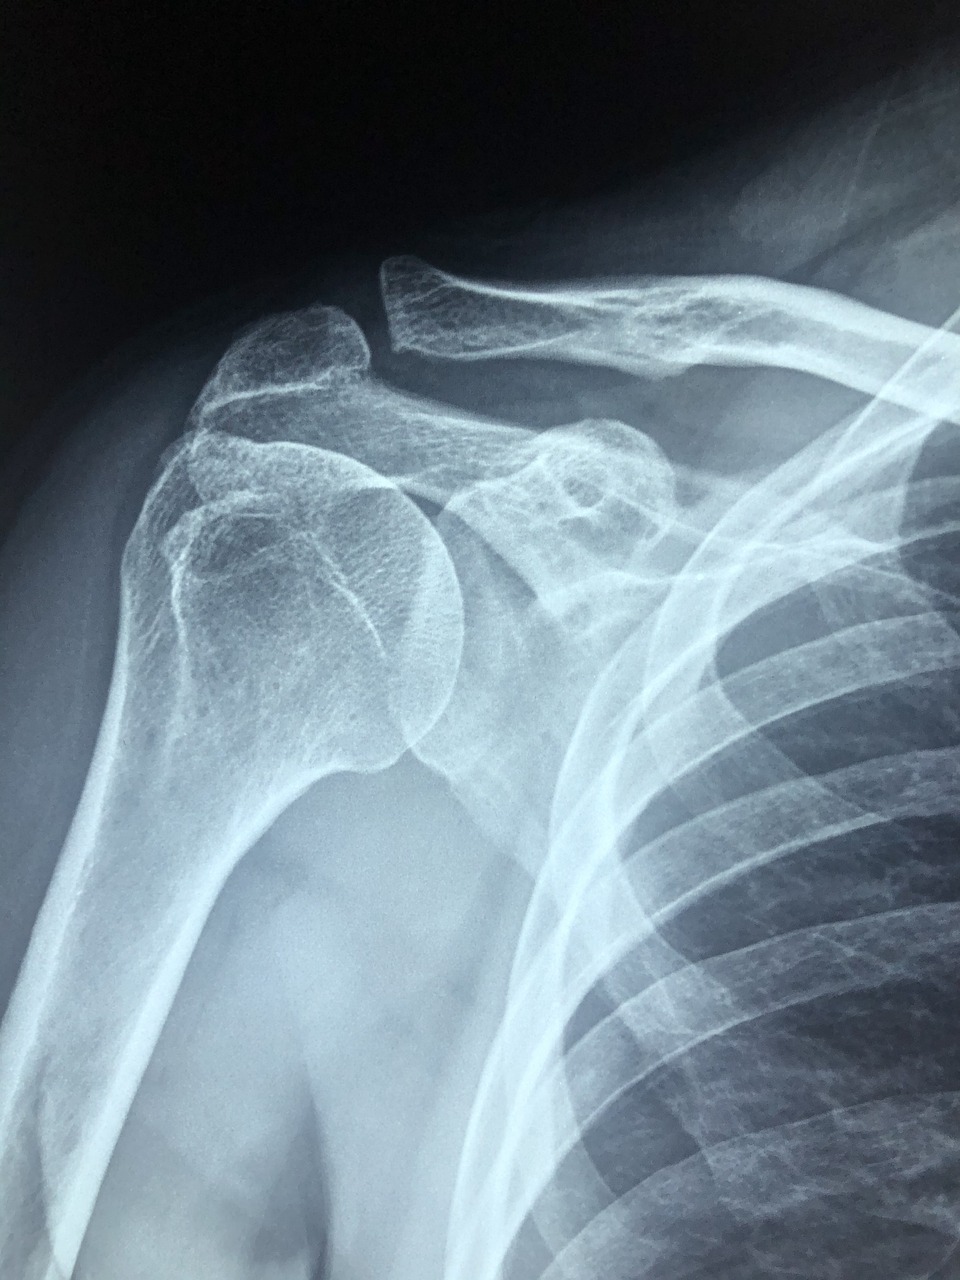

● 스테로이드 주사는 어깨 관절에 생긴 염증을 빠르게 가라앉히기 위해 사용하는 항염증 치료법입니다. 특히 회전근개염, 오십견, 석회성건염 등에서 급성 통증 완화에 많이 사용됩니다.

● 일반적으로 병원에서는 초음파 유도 하에 어깨 관절 내부에 직접 주사액을 주입합니다. 효과는 2~3일 내에 나타나며, 통증이 눈에 띄게 줄어드는 경우가 많습니다.

● 어깨 주사치료 부작용 중 가장 주의해야 할 점은 반복 투여에 따른 조직 손상입니다.

● 스테로이드 성분은 강력한 항염효과가 있는 만큼, 지나치게 자주 사용하면 힘줄(건) 약화와 연골 손상이 일어날 수 있어요. 특히 회전근개 파열 위험이 높아질 수 있으며, 이는 이후 수술로 이어질 가능성도 있습니다.